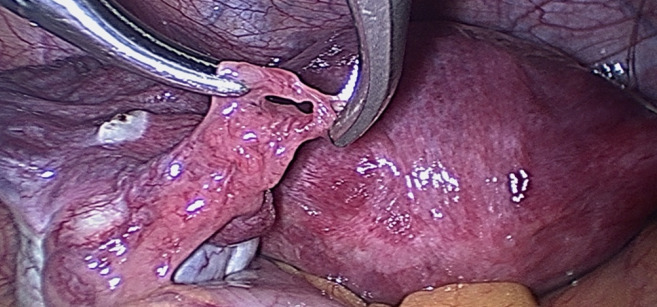

Materials and methods: The investigation was carried out in five medical centres in China and France from February to July 2021 and included reproductive-age patients who underwent gynaecological laparoscopy. Subtle abnormalities included Hydatid of Morgagni (HM) , fimbrial agglutination, tubal diverticula, accessory ostium, fimbrial phimosis, and accessory fallopian tube.

Results: 642 patients were enrolled in the study and 257 (40.0%) were diagnosed with subtle tube abnormalities. Hydatid of Morgagni was the most common abnormality (22.7%; n=146), followed by fimbrial agglutination (19.8%; n=127), tubal diverticula (6.9%; n=44), accessory tube (2.0%; n=13), and tubal accessory ostium (1.9%; n=12). Fimbrial phimosis was the least common abnormality (0.3%; n=2). The prevalence of subtle fallopian tube abnormalities was significantly higher among infertile patients (188/375, 50.1%) than those without history of infertility (69/267, 25.8%, ᶍ2=38.332, P=0.000). 209 patients were diagnosed with endometriosis during surgery, and the prevalence of subtle abnormalities was significantly higher in the endometriosis group than in those without endometriosis (61.2%, [128/209] vs. 29.8% [129/433], ᶍ2=58.086, P=0.000).

Abstract Image